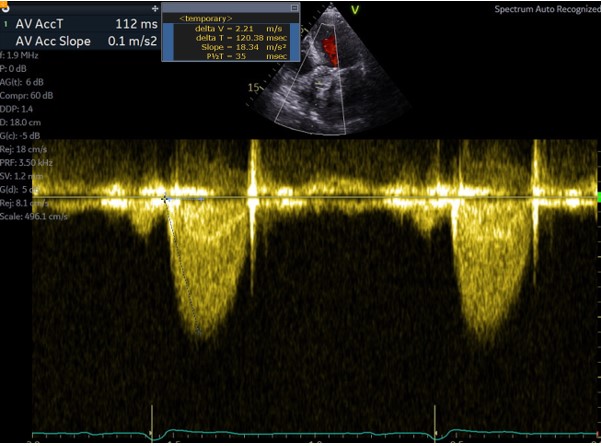

@echo_batman @echoguru @sturwohld @Becho2106 @dr_benoy_n_shah @iamritu @NMerke Here I have used two methods, one using duration - 112 ms, and the other using the time to peak - 120 ms

English